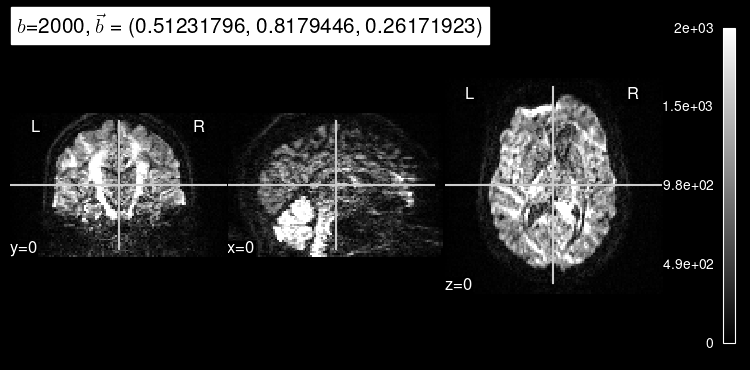

Here’s the original DW map, for reference:

plot_dwi(test_data, dmri_dataset.affine, gradient=test_b);